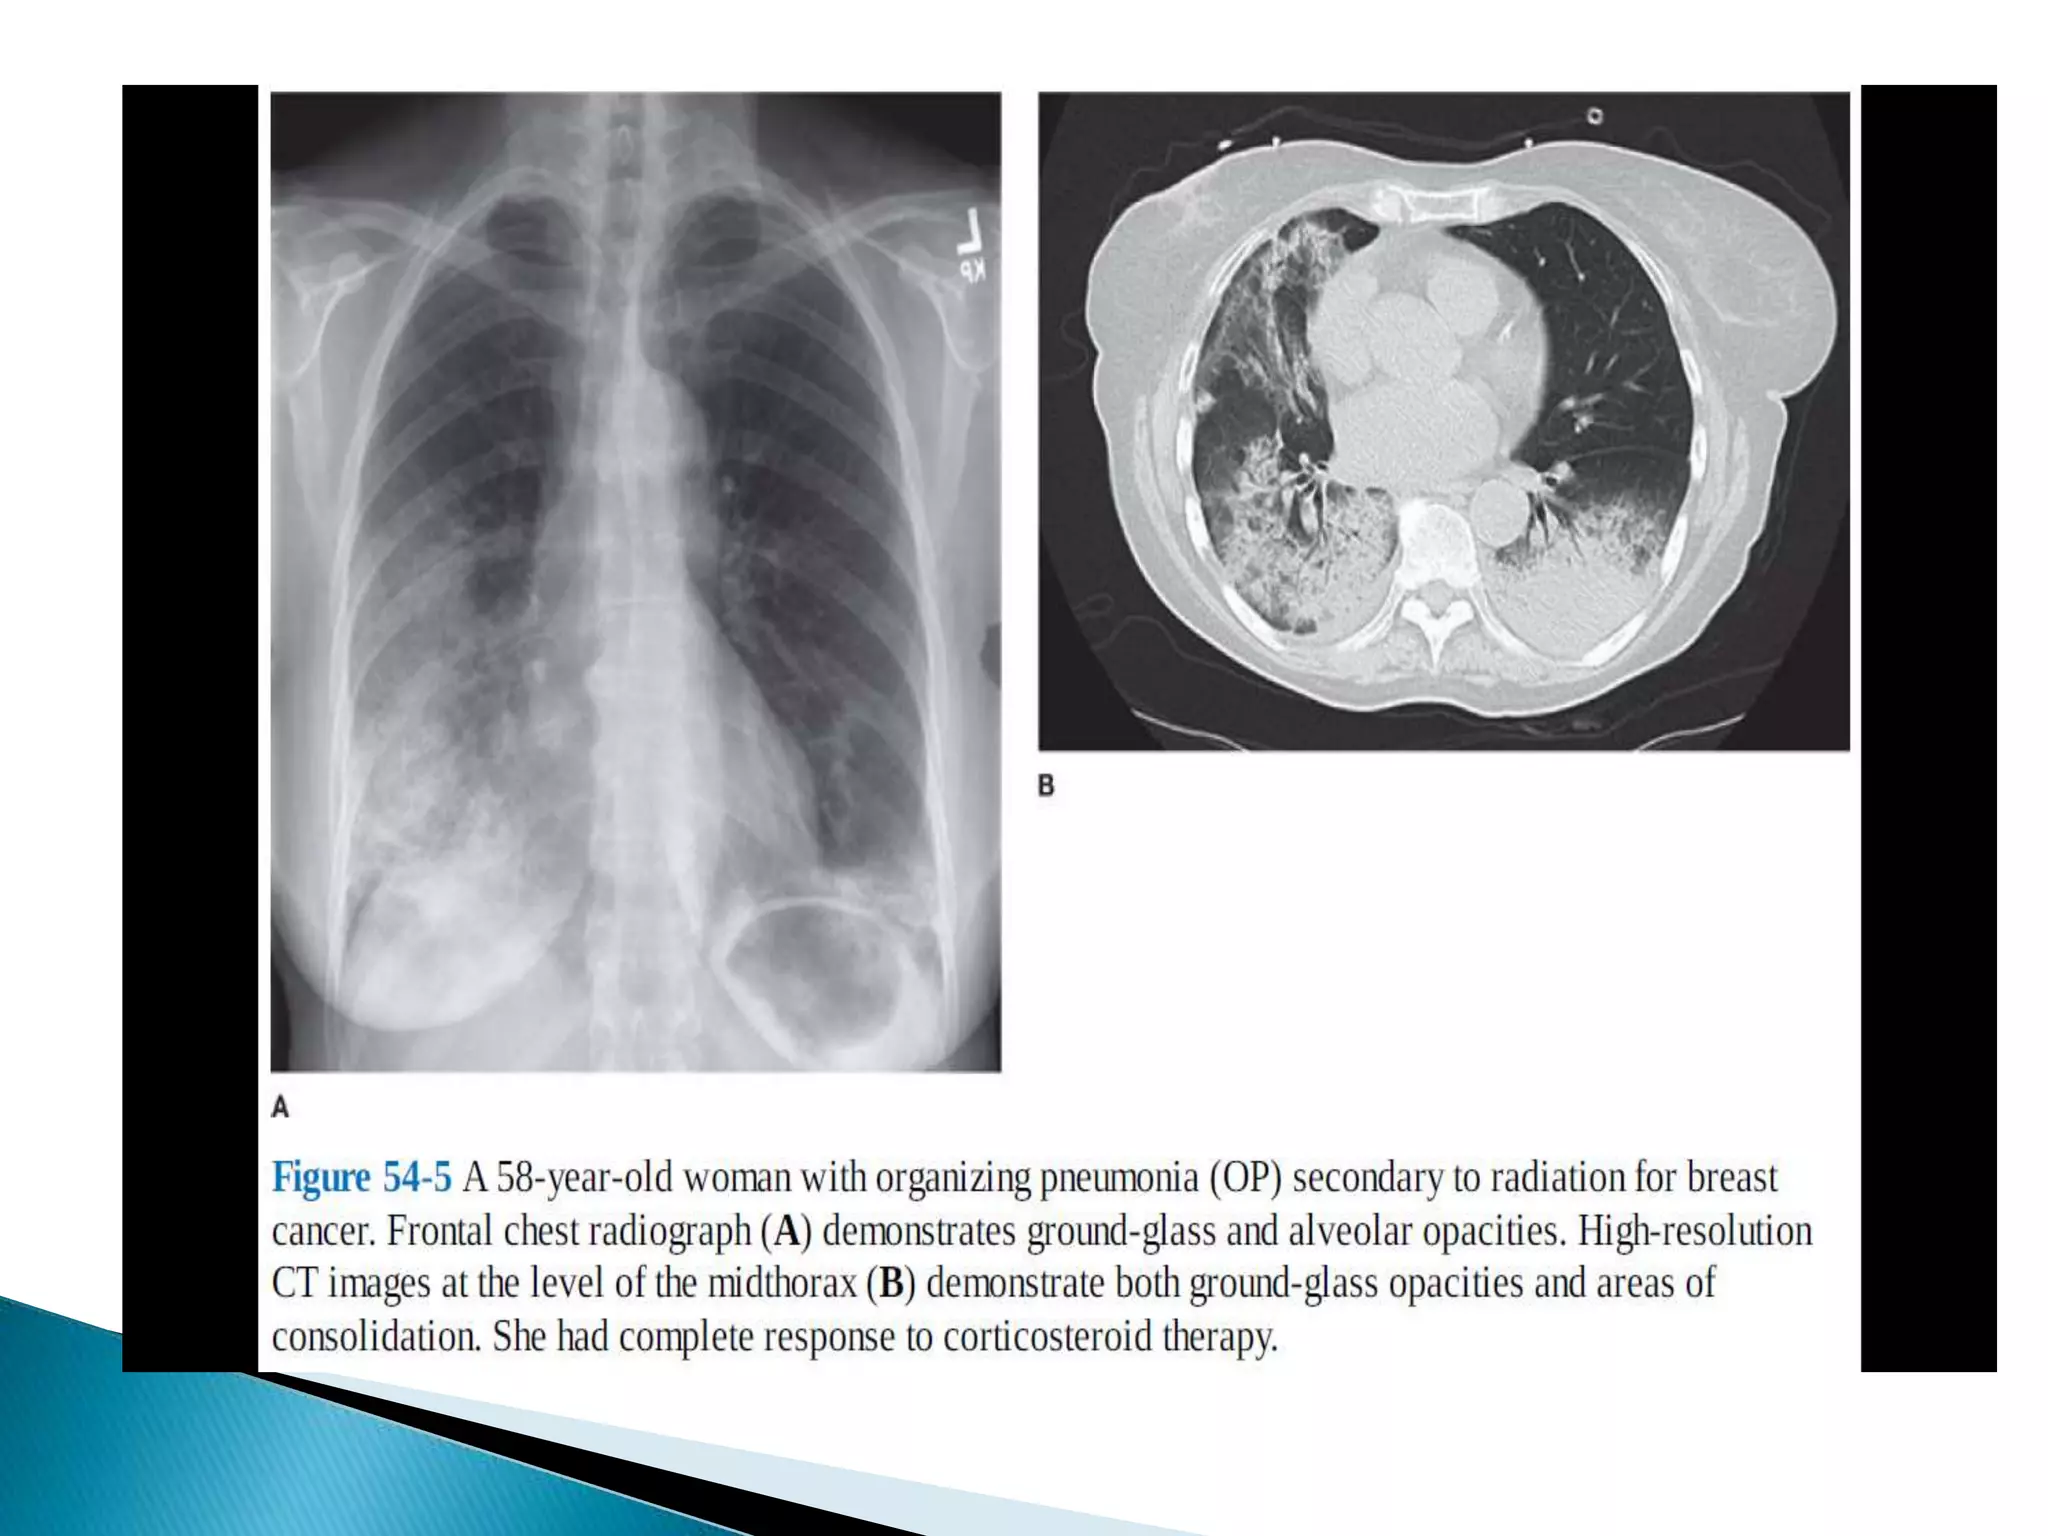

 Peripheral alveolar opacities are typical

findings in organizing pneumonia and

chronic eosinophilic pneumonia